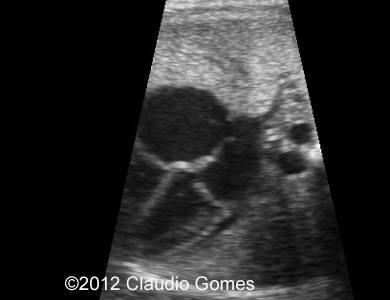

Images 8-11: Persistent right umbilical vein and Inferior vena cava interruption with continuity of the flow via Azygos vein on grayscale and color Doppler

Fig8

Fig9

Fig10

Fig11